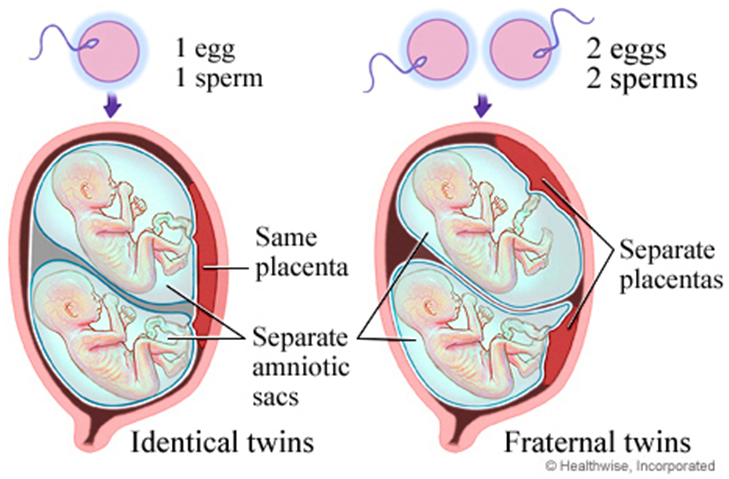

சிலசந்தர்ப்பங்களில், மாதவிடாய்சுழற்சியின்போதுஒன்றுக்கும்மேற்பட்டமுட்டைகள்வெளியிடப்படுகின்றன, மேலும்ஒவ்வொன்றும்விந்தணுக்களால்கருவுறுகின்றன, இதன்விளைவாகஒன்றுக்குமேற்பட்டகருக்கள்கருப்பையில்வளரும். இந்தவகையானகர்ப்பத்தின்விளைவாகசகோதரஇரட்டையர்கள் (ஒரேமாதிரிஇல்லாதவர்கள்ஆவார்கள்).

ஒருகருவுற்றமுட்டைமற்றொன்றில்பிளவுபடுகிறது, இதன்விளைவாகஒரேமாதிரியானபலகருக்கள்உருவாகின்றன.இந்தவகையானகர்ப்பத்தின்விளைவாகஒரேமாதிரியானஇரட்டையர்கள் (அல்லதுஅதற்குமேற்பட்டவர்கள்).ஒரேமாதிரியானஇரட்டையர்கள்சகோதரஇரட்டையர்களைவிடகுறைவாகவேகாணப்படுகின்றன.

ஒரேமாதிரியான மற்றும் ஒரேமாதிரியாக இல்லாத இரட்டையர்களுக்கு வேறுபாடு என்ன?

- ஒரே மாதிரியான குழந்தைகள் மோனோ சைகோடிக் (Monozygotic) என்று அழைக்கப்படுகின்றன. மோனோ சைகோடிக் உடன் பிறப்புகள் ஒருமுட்டையிலிருந்து வருகிறார்கள். இந்தவழக்கில், முட்டை ஒரு விந்தணுவால் கருவுற்றது, பின்னர் இரண்டு அல்லது அதற்குமேற்பட்ட கருக்களாகப்பிரிக்கப்படுகிறது. இந்தக்குழந்தைகள் அனைத்தும் ஒரேபாலினமாக இருக்கும். அவை அனைத்தும் ஒரேமாதிரியான மரபணுக்களைக்கொண்டிருக்கும்.

- ஒரே மாதிரி இல்லாத இரட்டையர்கள் டிசைகோடிக் (dizygotic) என்று அழைக்கப்படுகிறார்கள். மூன்று அல்லது அதிகமடங்குகள் பாலிஜிகோடிக் (polyzygotic) ஆகும். இந்தவழக்கில் ஒவ்வொருமுட்டையும் ஒருதனி விந்தணு மூலம் கருவுற்றது. குழந்தைகள் ஒரேபாலினமாக இருக்கவேண்டிய அவசியமில்லை மற்றும் வெவ்வேறு மரபணுக்களைக்கொண்டுள்ளனர்.

உயிரணுக்களின் ஆரம்பநிலையில் கருப்பையில் பதியும்போது, கருப்பையின் புறணி நஞ்சுக்கொடி எனப்படும் மற்றொருவகை திசுக்களை வளர்க்கத்தொடங்குகிறது. வளரும்கரு தொப்புள்கொடி எனப்படும் குழாய் மூலம் நஞ்சுக்கொடியுடன் இணைக்கப்பட்டுள்ளது. நஞ்சுக்கொடி வளர்ந்துவரும் கருவுக்கு அனைத்து ஊட்டச்சத்துக்களையும் இரத்தத்தையும் வழங்குகிறது. அம்னோடிக்சாக் (amniotic sac) எனப்படும் திரவப்பைக்குள் கருவளர்கிறது. அம்னோடிக்சாக்கின் உள்புறணி அம்னியன் என்று அழைக்கப்படுகிறது. வெளிப்புறபுறணி chorion என்று அழைக்கப்படுகிறது, மற்றும் நஞ்சுக்கொடியுடன் இணைக்கிறது.எடுத்துக்காட்டாக:

- இரட்டையர்கள் டைகோரியானிக் டயம்னியோடிக் ஆக இருக்கலாம். இரட்டையர்களுக்கு தனித்தனி அம்னியன்கள் மற்றும் கோரியான்கள் உள்ளன. இதுகுறைந்த ஆபத்துள்ள இரட்டைகர்ப்பத்தின் வகை.

- இரட்டையர்கள் மோனோ கோரியோனிக்டயம்னியோடிக் ஆக இருக்கலாம். இரட்டையர்கள் ஒரேகோரியன் மற்றும் நஞ்சுக்கொடியைப்பகிர்ந்து கொள்கிறார்கள். அவைதனித்தனி அம்னோடிக்பைகளில் வளரும்.

- இரட்டையர்கள் மோனோ கோரியோனிக் மோனோ அம்னியோடிக் ஆக இருக்கலாம். இரட்டையர்கள் ஒரே அம்னியன், கோரியன் மற்றும் நஞ்சுக்கொடியைப்பகிர்ந்து கொள்கிறார்கள்.